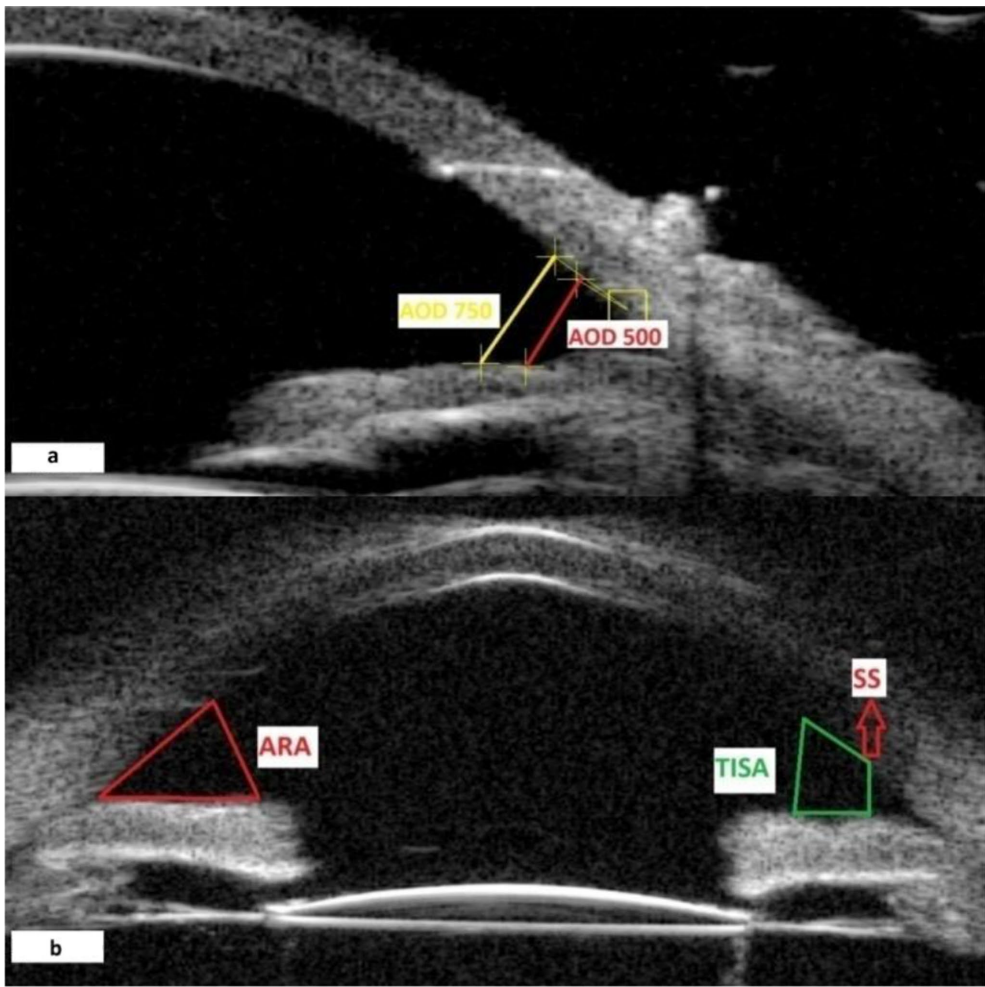

研究采用前瞻性队列设计,纳入34例单眼PCO患者(均植入AcrySof SA60 IOL)。使用50MHz UBM探头在暗室条件下测量鼻/颞侧前房参数,包括:前房角宽度(ACA)、500/750μm处角开放距离(AOD500/AOD750)、小梁-虹膜空间面积(TISA500/TISA750)等。所有患者接受标准化Nd:YAG激光治疗(能量0.9-3.0mJ/脉冲,囊膜开口4.0-4.5mm),术前术后均予溴莫尼定预防性降眼压。

激光术后1周即出现显著改变:鼻侧ACA从42.50±4.18°增至45.62±4.73°(p=0.001),颞侧TISA750从0.52±0.09mm2升至0.58±0.09mm2(p=0.001)。这种增宽效应持续至术后1月且无衰减(所有参数p>0.05),提示其并非暂时性炎性反应。研究首次报道的500μm处角隐窝面积(ARA500)增加尤为突出(0.15±0.03mm2→0.19±0.04mm2, p<0.001),该区域正是房水流出的关键解剖通道。